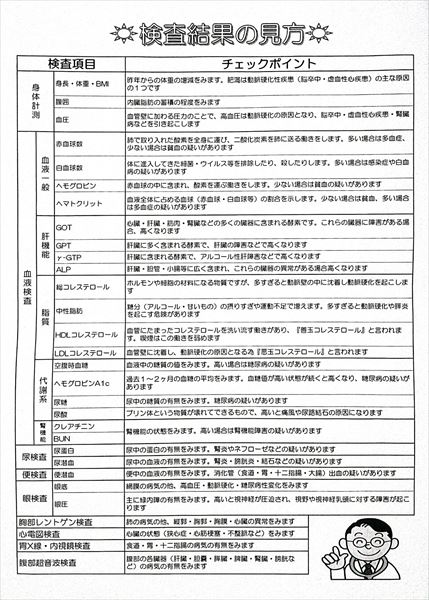

0140 健康診断結果

0109 24.7.29健康診断=pdf

0108 ①22.8.23荒尾市民病院=pdf ②2023-08-21健康診断結果.pdf 8/10(木)受診 荒尾市民病院